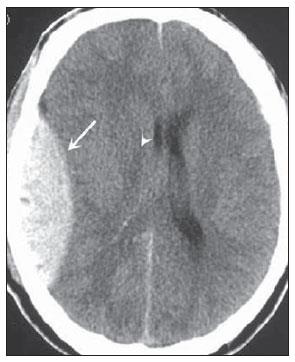

Analise a tomografia abaixo e assinale a alternativa que indique, corretamente, o achado radiográfico:

http://www.rb.org.br/detalhe_artigo.asp?id=2613&idioma=Portugues